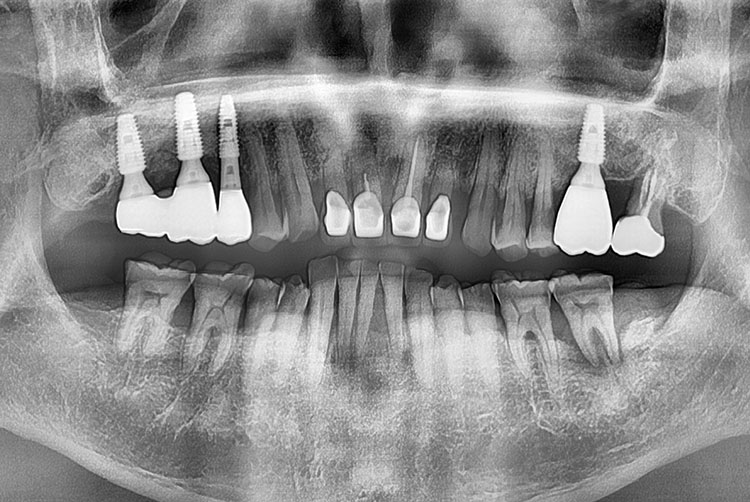

[임플란트] 임플란트

cf67625cd552c18b7da2ebb068d92536.jpg

치료전 : 2014-08-21

세종치과는 많은 환자와 다양한 케이스를 바탕으로 항상 편안한 임플란트 수술을 제공하고자 노력하고,

오래동안 튼튼히 쓸 수 있는 임플란트 수술을 가장 큰 목표로 삼고 있습니다.